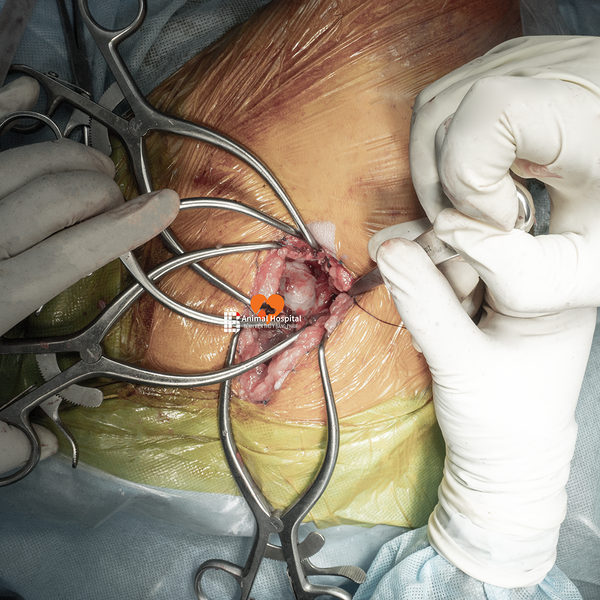

🔧 Giải pháp phẫu thuật | Total Hip Replacement (THR)

Sau khi đánh giá tổng thể tình trạng thoái hóa khớp háng ở chó, team bác sĩ tại Bệnh Viện Thú Y Bằng Phạm đã quyết định thực hiện thay khớp háng toàn phần bằng hệ thống tiên tiến 𝐁𝐥𝐮𝐞𝐒𝐀𝐎 𝐁𝐢𝐨𝐧𝐢𝐜 𝐇𝐢𝐩 – một trong những công nghệ hàng đầu hiện nay trong lĩnh vực cấy ghép khớp ở thú y.

✅ Đội ngũ phẫu thuật

- Bác sĩ phẫu thuật chính: Phạm Bằng, Nguyễn Đình Chuẩn, La Hạo Kiên